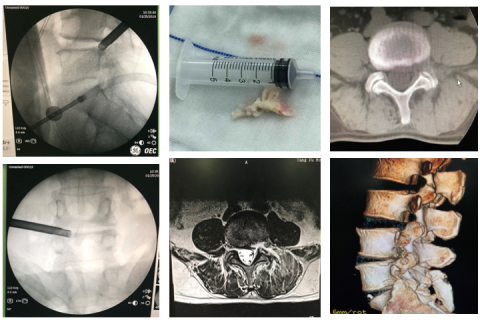

2.以上疗效不佳,可进行椎间孔镜微创治疗;

3.椎体压缩性骨折:经皮椎体成形术(球囊骨水泥)、经皮钉棒内固定治疗压缩性骨折。